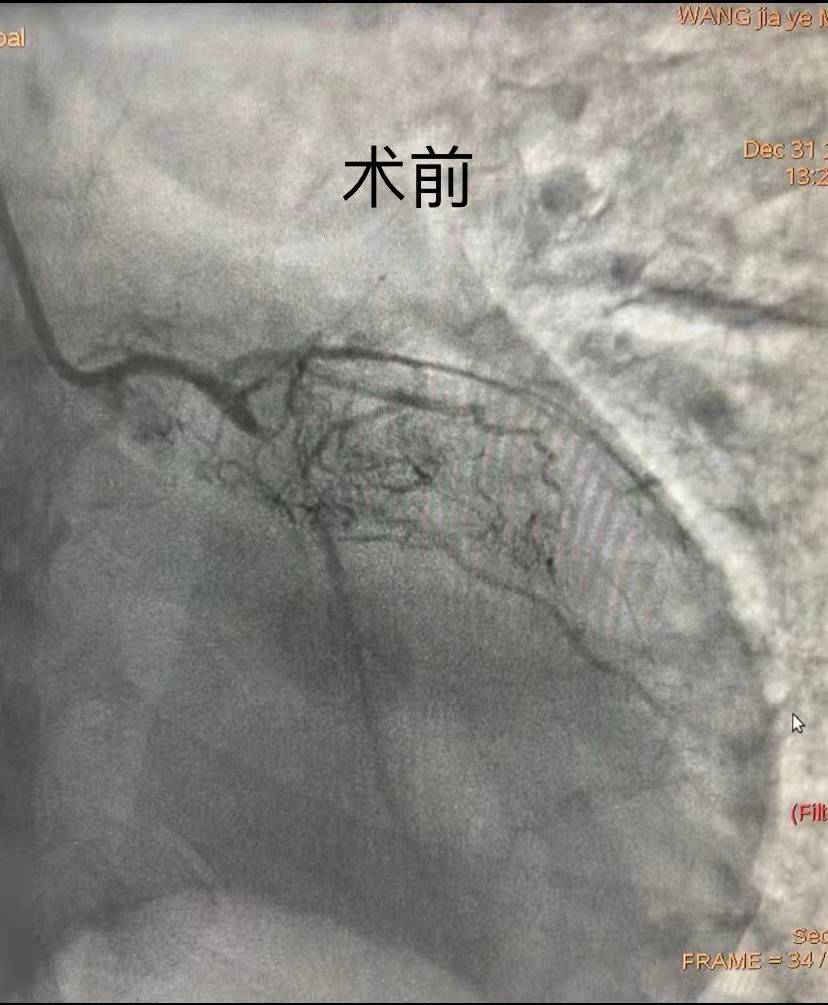

時(shí)間就是生命,時(shí)間就是心肌。在取得患者及家屬的理解及配合后,副院長(zhǎng)汪念東、副主任徐先進(jìn)及主任助理農(nóng)彥林帶領(lǐng)心血管內(nèi)科介入團(tuán)隊(duì)制定嚴(yán)密的救治方案及應(yīng)急預(yù)案,為患者施行緊急冠狀動(dòng)脈造影,證實(shí)多支血管彌漫性病變、LAD(冠狀動(dòng)脈前降支)慢性閉塞、LCX(冠狀動(dòng)脈左回旋支)近端次全閉塞、RCA(右冠狀動(dòng)脈)近端嚴(yán)重狹窄達(dá)90%。因患者血流動(dòng)力學(xué)極其不穩(wěn)定,用大劑量血管活性藥物維持基礎(chǔ)血壓的效果并不理想,團(tuán)隊(duì)為患者應(yīng)用IABP泵,完成術(shù)前生命支持系統(tǒng)。

團(tuán)隊(duì)綜合考慮后判斷,LCX是此次心肌梗死的“元兇”。開(kāi)通病變部位的機(jī)會(huì)只有一次,必須做到“快、準(zhǔn)、狠”。汪院長(zhǎng)團(tuán)隊(duì)經(jīng)驗(yàn)豐富,技術(shù)嫻熟,導(dǎo)絲小心通過(guò),球囊充分?jǐn)U張,最后在病變部位植入支架,所有操作一氣呵成。復(fù)查造影顯示,病變部位狹窄小于10%,手術(shù)獲得成功。